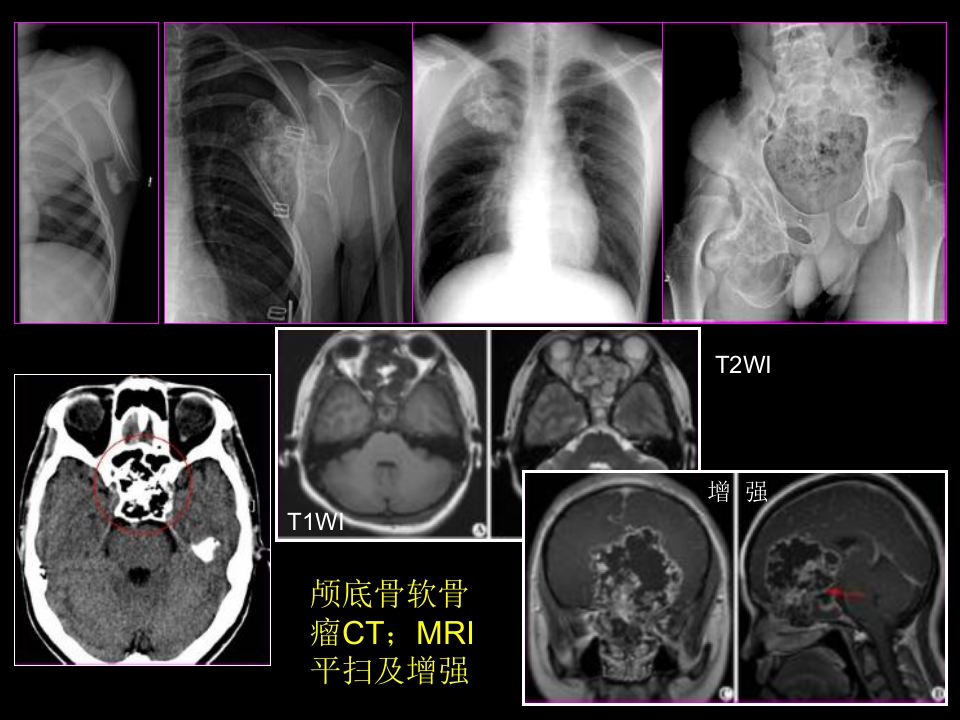

骨肿瘤影像学诊断